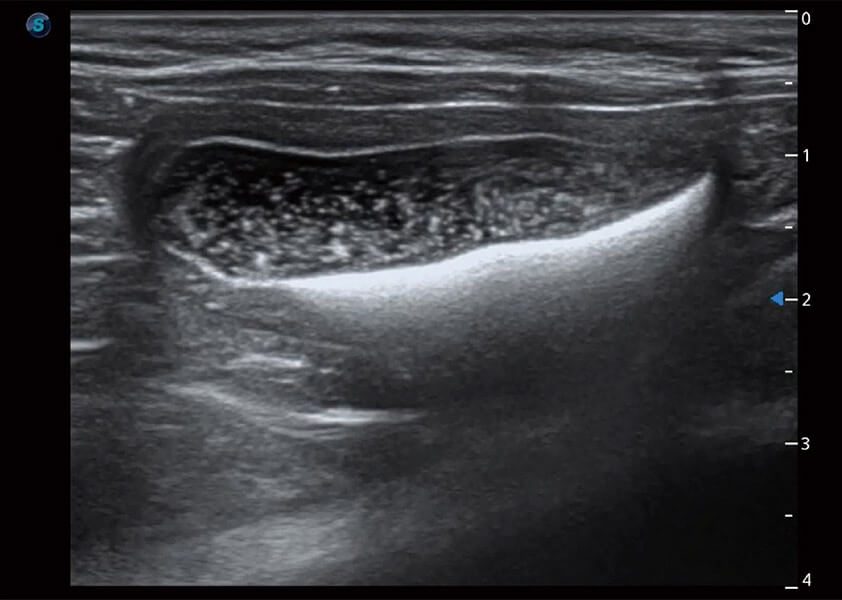

ProPet 60 作为一款高端台式动物超声设备,为动物医生的日常诊断提供了一系列贴合动物临床需求、解决临床实际问题的高级成像功能。凭借全系列高清探头,满足医生对腹部、心脏、生殖、浅表、肌骨等成像的所有需求,切实帮助您提升检查效率,提高诊断信心。

ProPet 60 尊享版

兽用彩色多普勒超声诊断系统